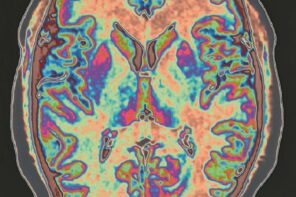

The brain is more powerful than we know. Our subconscious consists of inert knowledge of no known origin, yet also blind and impulsive desires. Once … Continue reading The Placebo Effect